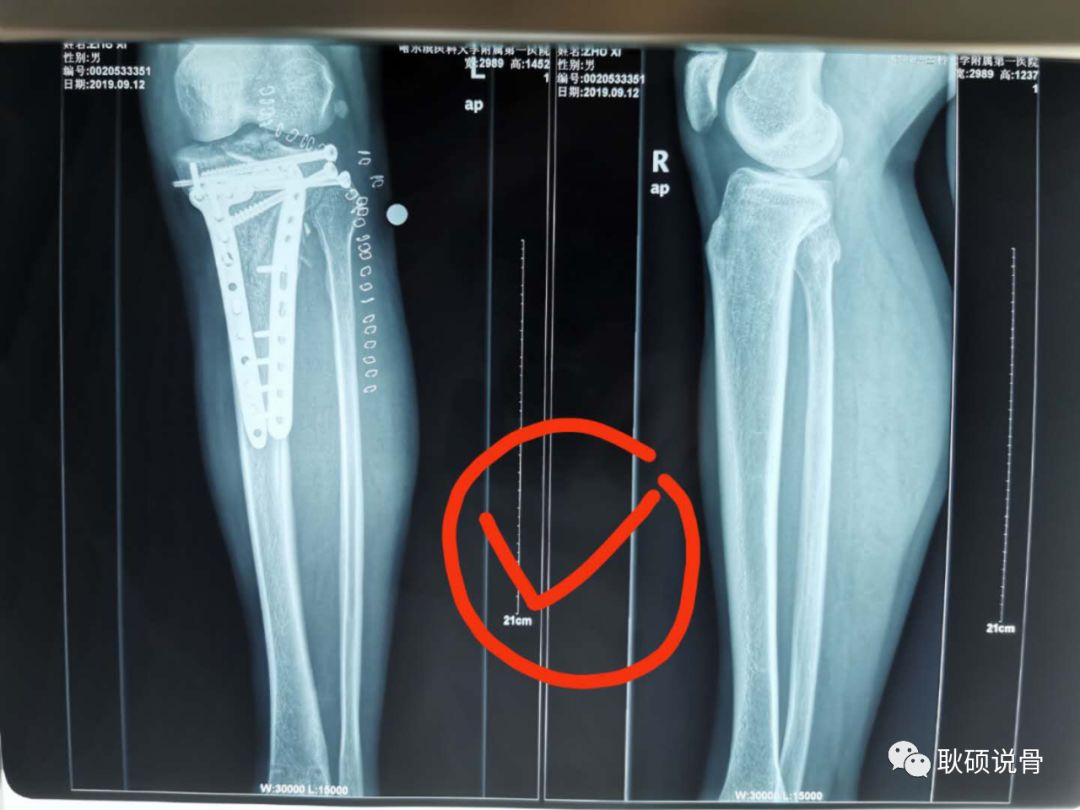

3、打开手机相机拍照!不要直接用微信拍照!调整距离拍照,保证横平竖直,整个片子内容填满整个屏幕,就像这样: